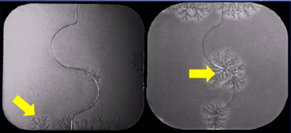

目前已经上市的固体分散体技术产品包括诺华公司的抗真菌药灰黄霉素、以及西安杨森公司的抗真菌药伊曲康唑等等,真正上市的SD品种并不多,阻碍其广泛商业化的因素有:扩大生产问题以及贮存期的稳定性等,而SD的不稳定性会显著影响药物的溶解性、稳定性以及相应的制剂制备工艺等。例如用于治疗帕金森症的罗替戈汀贴剂,贴剂表面在存储过程中表面会出现雪花状结晶,结晶现象严重影响了该贴剂的药物递送速率,影响药效的发挥,该产品在2008年被迫从美国市场撤回,直到2012年才重新获批。